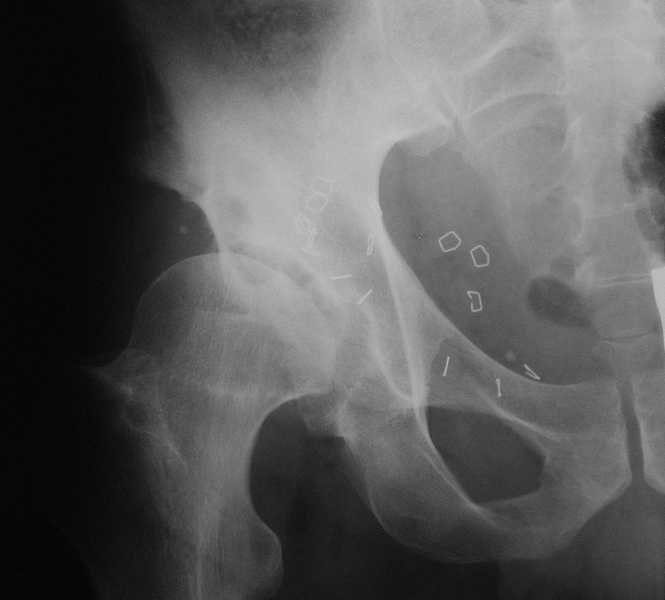

Пациент 40 лет страдает болями в правом тазобедренном суставе более года, хромота, ночные боли.

2 года назад была выполнена лапароскопическая герниопластика косой паховой грыжи.На снимках на фоне двухсторонних диспластичных тазобедренных суставов кистозные полости-фиброзная дисплазия? Возникает тактическая задача- пациент нуждается в экскохлеации образования и пластике или же в одномоментном ТЭП.Левый тазобедренный сустав не беспокоит.